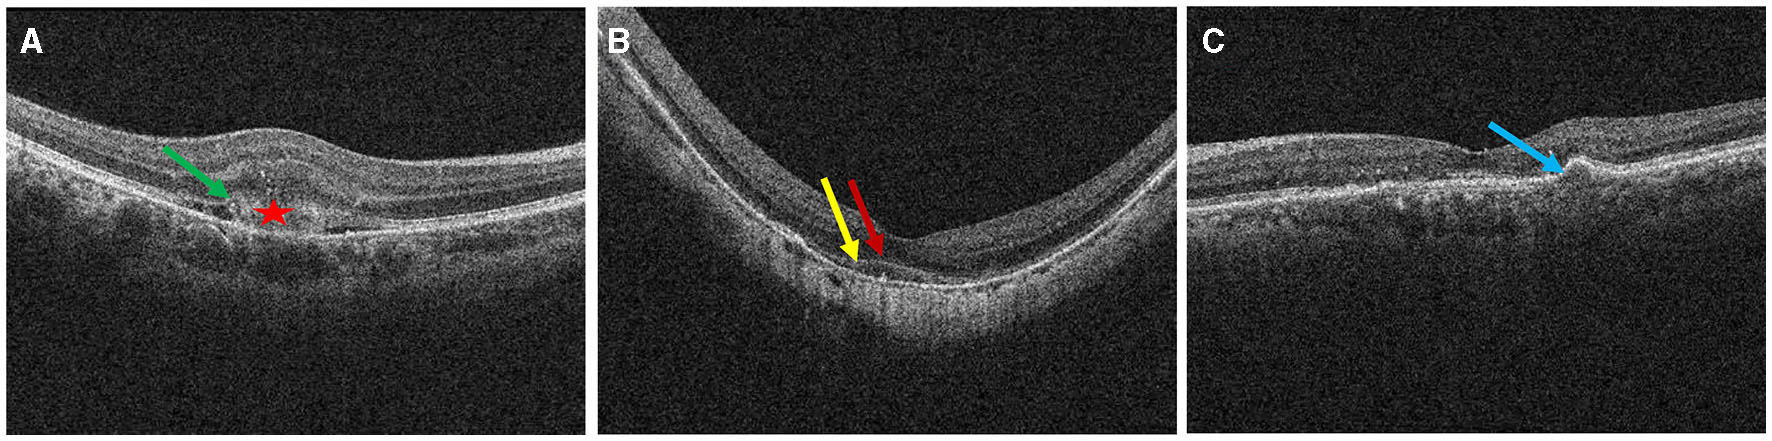

Figure 3

Definition of outer retinal characteristics associated with MNV activity using OCT. Subretinal hyperreflective exudation was defined as the presence of areas of high reflectivity that are located outside the RPE but within the retinal pigment epithelium [⋆ in (A)]. EZ/ELM interruption was defined as the absence or discontinuity of EZ/ELM hyperreflective lines above MNV lesions [(A), green arrow]. EZ/ELM elevation was defined as elevated EZ/ELM hyperreflective lines above MNV lesions (B) (EZ, yellow arrow; ELM, red arrow). RPE elevation was defined as a highly reflective band over the MNV lesions on OCT and was continued with the RPE monolayer [(C), blue arrow]. RPE interruption was identified in (A).